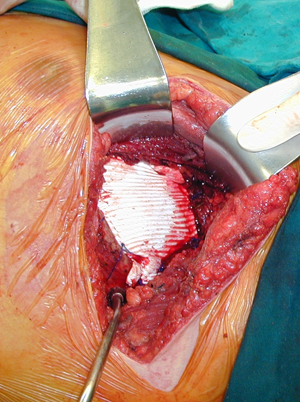

Εικόνα 4

Αποκατάσταση του θωρακικού τοιχώματος με την τοποθέτηση συνθετικού μοσχεύματος από πολυ-τετρα-φλουορο-αιθυλένιο ( Poli-tetra-fluoro-ethelene )